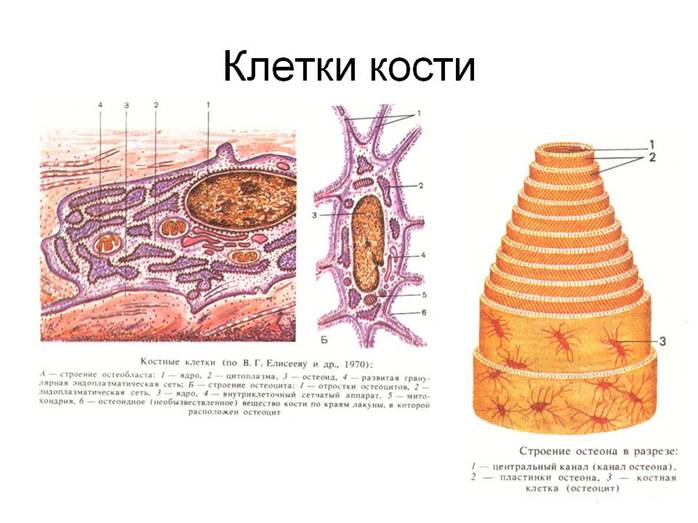

Структура грубоволокнистой костной ткани: наглядные примеры